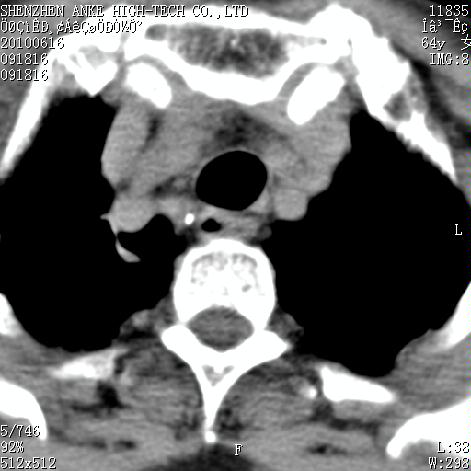

标题: CT27132:患者女,64岁,颈部及全身多处包块,现觉吞咽困难4 [打印本页]

标题: CT27132:患者女,64岁,颈部及全身多处包块,现觉吞咽困难4

右侧甲状腺占位,肿瘤可能性大,癌

右侧甲状腺癌伴右颌下腺淋巴结转移

右侧甲状腺癌伴淋巴结转移

右侧甲状腺癌伴淋巴结转移可能性大

右侧甲状腺癌伴淋巴结转移可能性大。

右侧甲状腺癌伴右颌下腺淋巴结转移!建议增强!